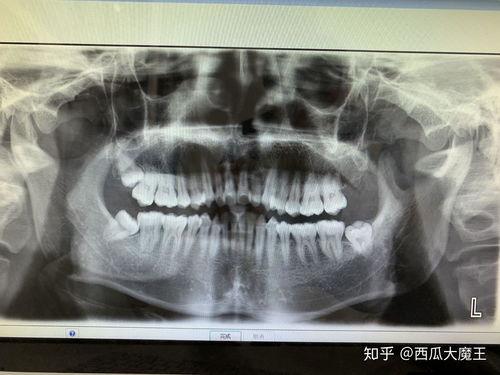

据统计,大约有70%的人都会长智齿,但并非每个人都会长出完整的四颗智齿。有些人的智齿可能因为空间不足而无法正常生长,甚至可能长歪或者长在牙龈下,这就需要通过拔除手术来解决。

在拔牙前,医生会先给你进行口腔检查,确认智齿的位置和生长情况。医生会给你进行局部麻醉,让你在拔牙过程中不会感到疼痛。